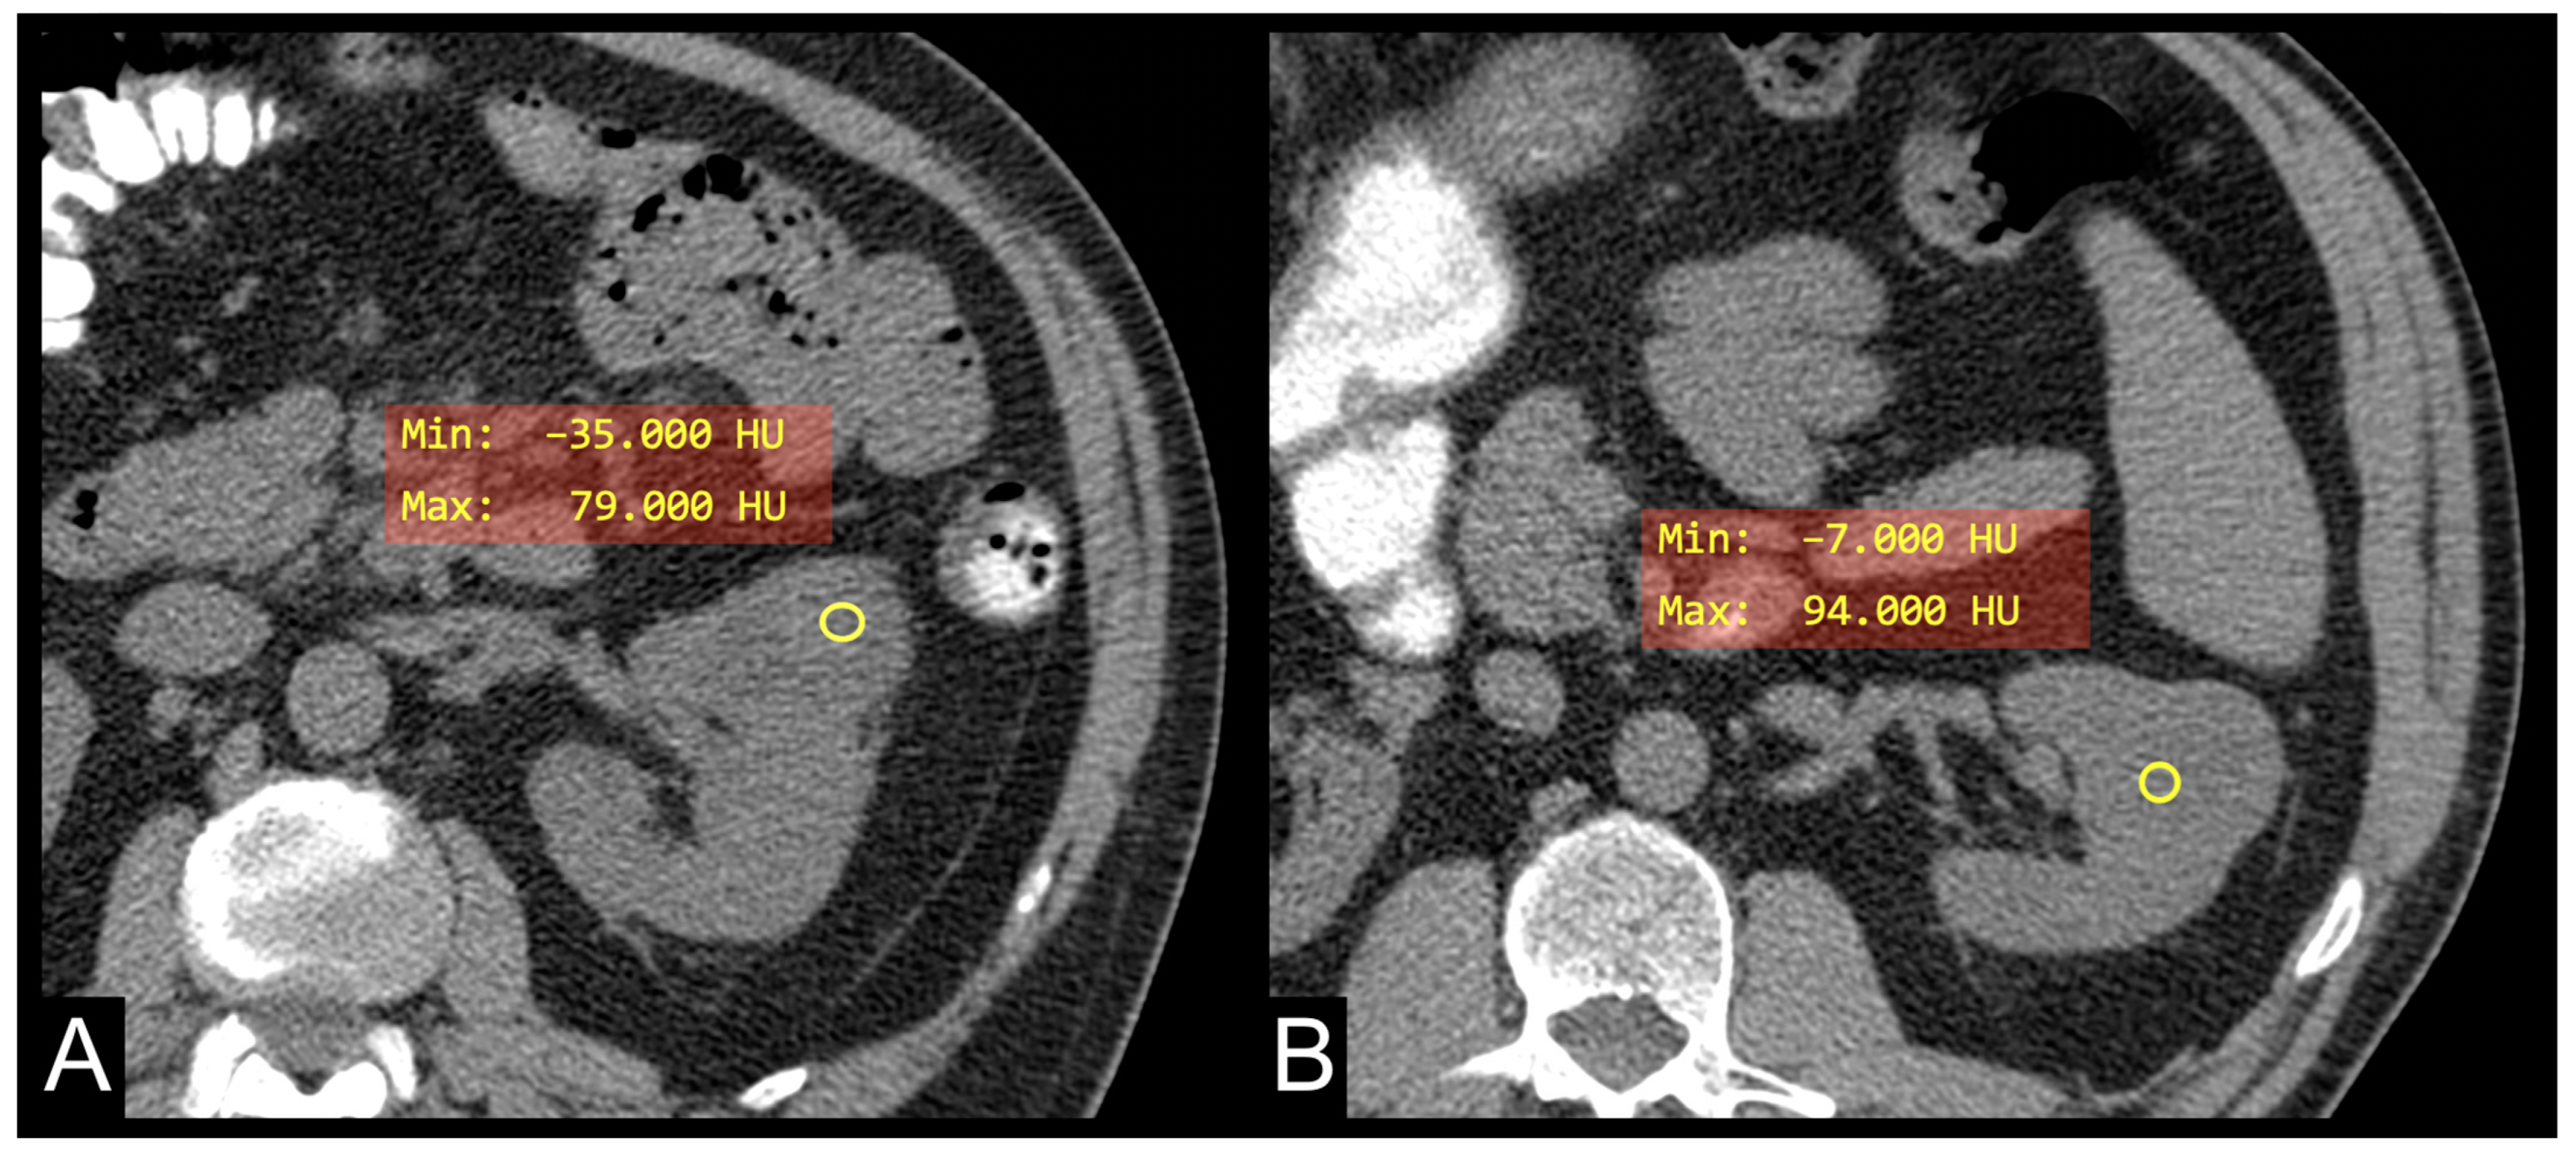

| HU Median Minimum Maximum | 36 (30, 40) −5 (−18, 3) 78 (67, 91) |

| HU minimum | −23 (−38, −13) | −3 (−11, 1) | 0.002 |

| HU minimum | −23 (−38, −13) | −6 (−16, 4) | 0.005 |